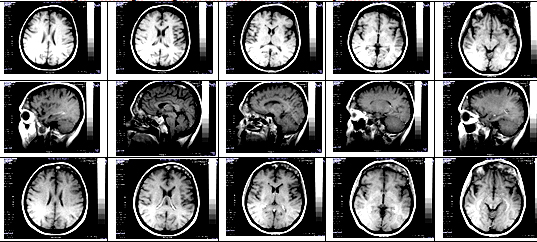

Slika 1. Scintigrafija celog tela sa 99mTc-DPD

(a), i ciljani scintigrami toraksa u dva pravca (b), i lobanje u

četiri pravca (c), juna 2014. RPO – desni zadnji polukosi; RAO –

desni prednji polukosi; ANT – prednji; LL – levi bočni; POST –

zadnji; RL – desni bočni.

Image 1. Whole-body scintigraphy with 99mTc-DPD (a), and targeted

thorax scintigrams in two directions (b), and the skull in four

directions (c), june 2014th. RPO – right posterior oblique; RAO –

right anterior oblique ; ANT – frontal; LL – left lateral; POST –

posterior; RL – right lateral.

Nalaz scintigrafije skeleta ukazivao je na nepravilno polje

patološke hiperakumulacije u predelu frontalne kosti i, nešto

slabijeg inteziteta, u regiji temporookcipitalnog spoja, s leve

strane; narušena arhitektonika prvih nekoliko rebara desnog

hemitoraksa sa lako pojačanom akumulacijom mestimično duž rebara,

intenzivnije u vertebralnim i sternalnim okrajcima, bez drugih mesta

patološke hiperakumulacije. Zaključuje se da patološka distribucija

radiofarmaka nije karakteristična za malignu bolest i indikuje se

radiografija lobanje.